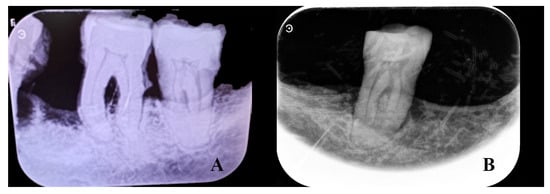

Figure 10.

Radiographic images of the lower left first and second molars (A), and the lower right second molar (B) of individual T4.2, showing evidence of alveolar bone resorption. The lower right second molar (B) also shows wear.

Examination of the splanchnocranium (Table A2), along with the skull, revealed an outward inclination of the incisors (Figure 7) and normal orbital dimensions, with a height of 31 mm and a breadth of 32 mm (Figure 7). According to Testut and Latarjet [26], the normal orbital range is 26–48 mm in height and 32–48 mm in breadth, with the lower end of this range being more typical among Spaniards. The mandible was very narrow (dolichognathous), with a mandibular index of 98.3 (Table A2). Absolute values indicate a morphological alteration with an increase in its anteroposterior measurement and a decrease in the laterolateral diameter, as is the case with the cranial measurements. These measurements suggest the presence of type III prognathism. The left hemimaxilla contained the second incisor, canine, and first premolar (the remaining dental elements were lost postmortem). The left hemimandible consisted of the second incisor, canine, first premolar, and first and second molars. The first incisor and second premolar had been lost during life (Figure 8). Examination of the dental elements on the left side highlights the large amount of tartar, which completely covers the lingual, labial, and occlusal surfaces of the preserved elements (Figure 8) and the presence of very little wear. On the right side, the hemimaxilla had retained the two incisors, the canine, and the first premolar (Figure 8). The right hemimandible had preserved the first and second incisors, the canine, and the second molar. The remaining elements of the right hemimandible were lost during life (Figure 8). In contrast to the left side, the right side showed tooth wear and very little tartar (Figure 8 and Figure 9). Significant resorption of the mandibular body was observed (Figure 9). Radiographic images confirm alveolar bone resorption in the mandible, with no evidence of periapical changes (Figure 10). In general, on the left side, the presence of minimal tooth wear and an extreme amount of tartar is notable. This could indicate the left dentition had not been used, probably because of unilateral mastication due to occlusal dysfunction; however, periodontal disease and hygiene differences cannot be excluded.